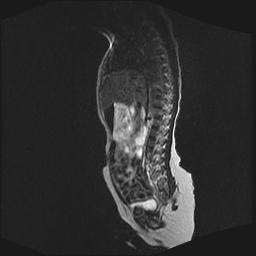

四个月的女婴,ct示脊膜膨出.

脂肪脊髓脊膜膨出

脊柱裂、脊膜膨出